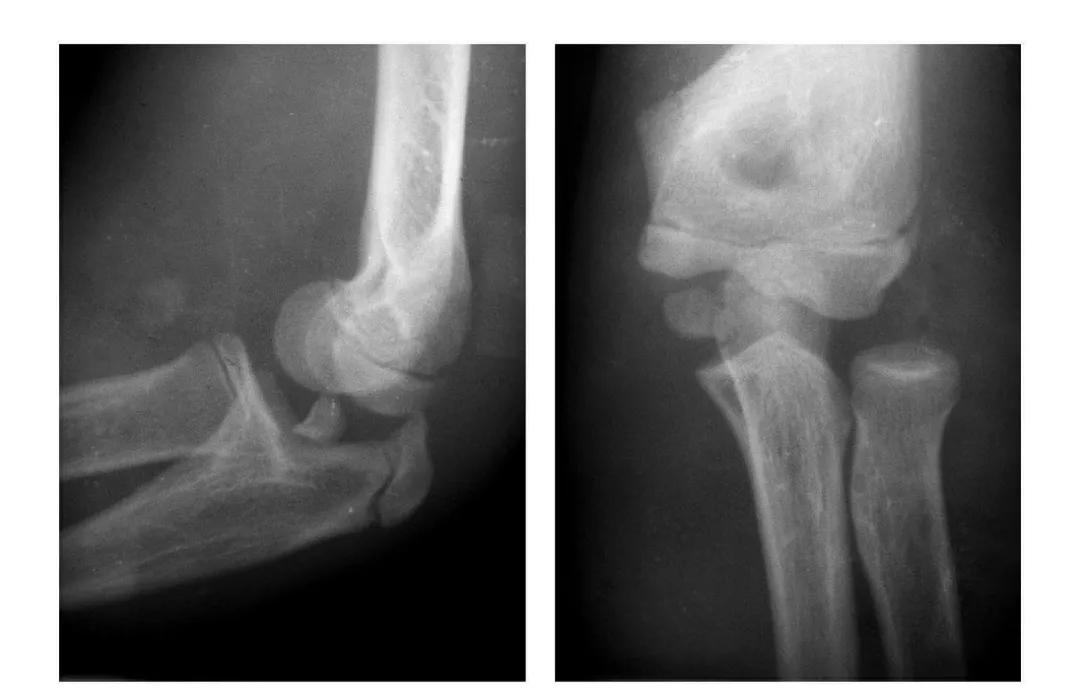

肱骨小头矢状面骨折

本病文献未见报道,即肱骨小头中部呈前后(矢状面)纵向骨折,将小头分为内外两部分。

本病因有明显的外伤史,即健侧小头正常,从而排除了先天因素。

例:肱骨小头矢状面骨折,折线波及外髁皮质骨折片,并鹰嘴突无移位骨折。